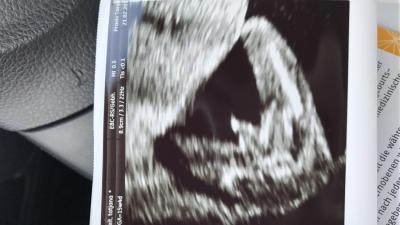

Wer hätte das gedacht :D Muttermund ist frei aber ein Hämatom ist nun da :/ also weiter schonen aber dafür gab es was tolles :D

Bild zu Haha - Forum für August - Mamis

Ich war ganz aufgeregt vor Freude :D ich war mir 100% sicher das es ein Mädchen ist :D